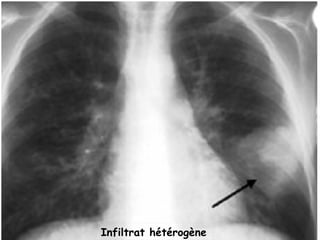

 RX thorax ( face + profil) :

   IMAGES LABILES :

- infiltrat parenchymateux hétérogène, ou péri hilaire

pouvant simuler des ADP.

- opacité systématisée rétractile lobaire ou

segmentaire, uni ou bilatérale, par bouchon muqueux.

- impaction mucoîde : bronchectasies pleines avec

aspect en doigt de gant

Infiltrat hétérogène